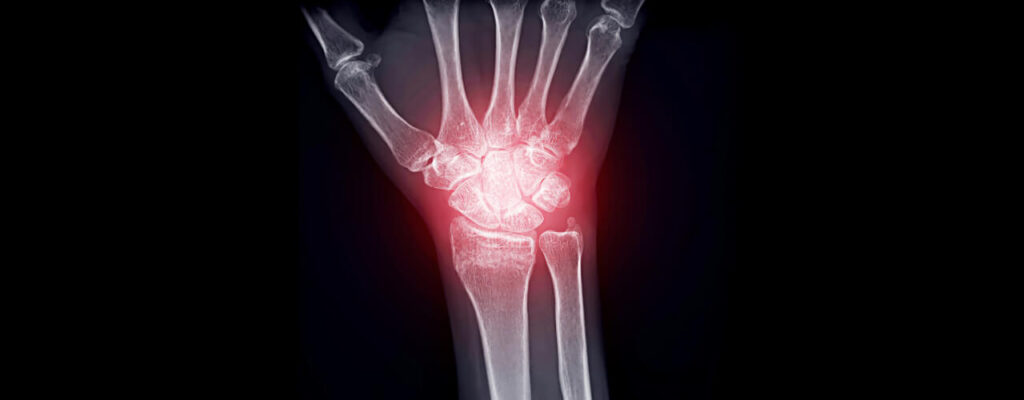

Arthritis can feel like a constant obstacle, making everyday activities challenging and painful. With stiffness, swelling, and discomfort often becoming part of daily life, many patients find themselves searching for a solution that truly works. At , we have proven arthritis treatment options to manage symptoms, improve mobility, and enhance overall quality of life.

Why Arthritis Needs a Comprehensive Approach

Arthritis isn’t just about joint pain—it’s a multifaceted condition that affects the entire body.